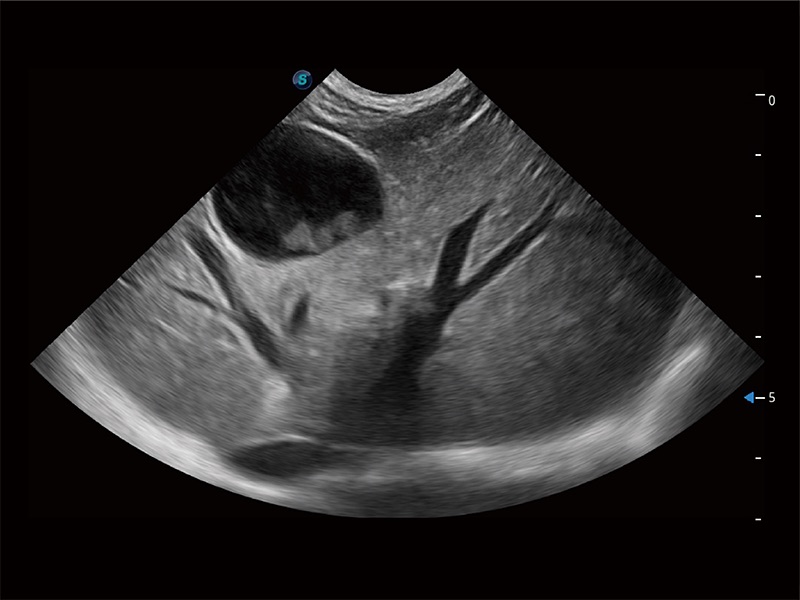

ProPet 80 全新的动物超声智能软件和丰富的探头群,为动物医生提供了高清晰度和精细分辨率的图像,无论在宠物、马科、畜牧还是实验室动物等应用中都可以轻松应对,为您的日常工作带来满意的体验。